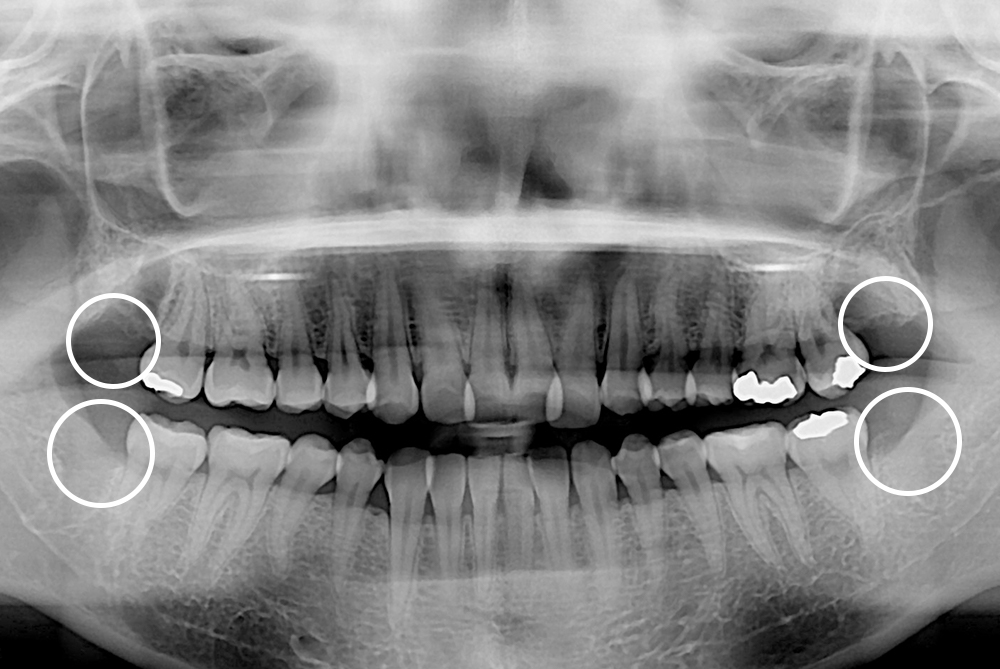

[사랑니] 매복 사랑니 발치

치료전 : 2018-06-04